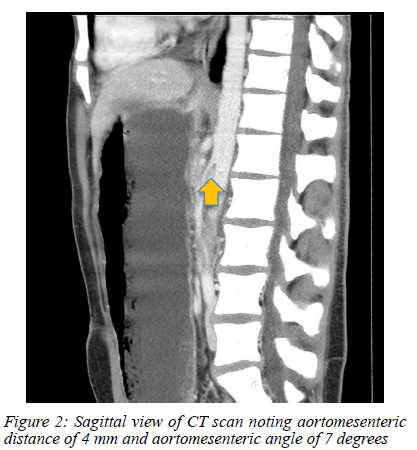

A nasogastric tube was passed and drained 1500 ml of bilious stomach content instantly. The patient was kept nil per mouth, with the nasogastric tube on free drainage, and intravenous fluid was administered. An urgent computer tomography (CT) scan with intravenous contrast was performed as the child was extremely uncomfortable despite analgesia and fluid resuscitation. The CT scan showed an obstruction at the third part of the duodenum with gross stomach and proximal duodenal distension (Figure 1). A clear transition point was seen between the abdominal aorta and superior mesenteric artery (SMA) origin with an aortomesenteric distance of 4 mm and an aortomesenteric angle of 7 degrees (Figure 2).

The CT findings were diagnostic of superior mesenteric artery syndrome (SMAS).

SMAS, otherwise known as Wilkie's syndrome, cast syndrome or chronic duodenal ileus, is a rare cause of upper gastrointestinal obstruction. Characteristically the third part of the duodenum is compressed by the aorta and SMA causing the typical symptoms of early satiety, anorexia, abdominal discomfort or pain, nausea, and vomiting. The normal SMA to aorta angle has been described to range from 38-56 degrees and 10-20 mm in length but in SMAS the angle is decreased ranging from 6-25 degrees and the length 2-8 mm.1'2 The patient had an angle of 7 degrees and 4 mm in length, which is likely why his obstruction was so severe.